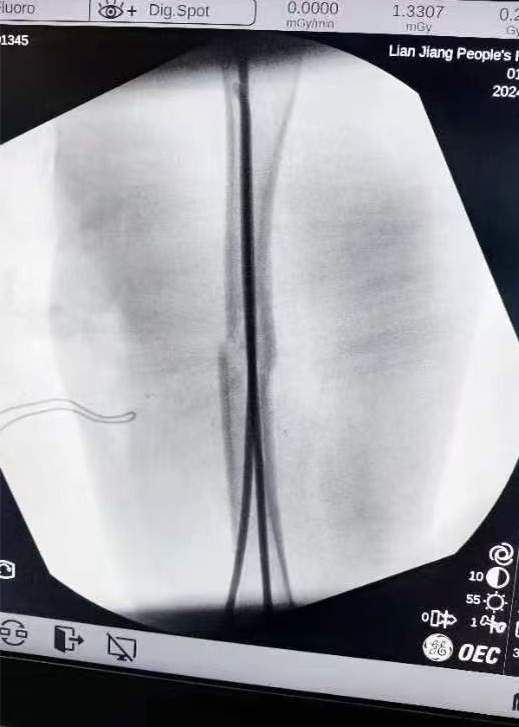

图片图片图片

跟骨粉碎性骨折闭合复位微创经皮穿针内固定